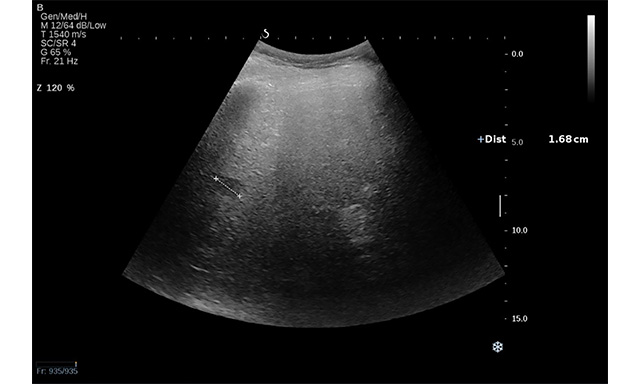

Figure 3. Conventional US revealed an isoechoic lesion with a hypoechoic halo in a 23-year-old woman diagnosed with non-alcoholic liver steatosis (arrow). CEUS examination followed, and, based on the contrast behaviour, the final diagnosis was focal nodular hyperplasia.